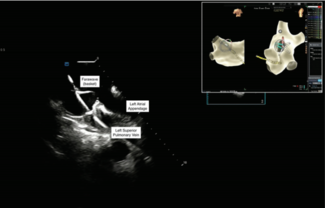

Eduardo B. Saad, MD, PhD, FHRS, FESC; Ronuk M Modi, MD

Drs Modi and Saad share their workflow for a safe and efficient zero-fluoroscopy PFA for pulmonary vein and posterior wall isolation using near-field intracardiac echocardiography (in the left atrium) and electroanatomic mapping.